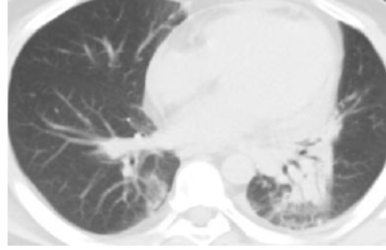

Bgr41Qgrm9eecp6p.jpg yBsczorQ4sRNn4Qo.jpg

放射野内条索影